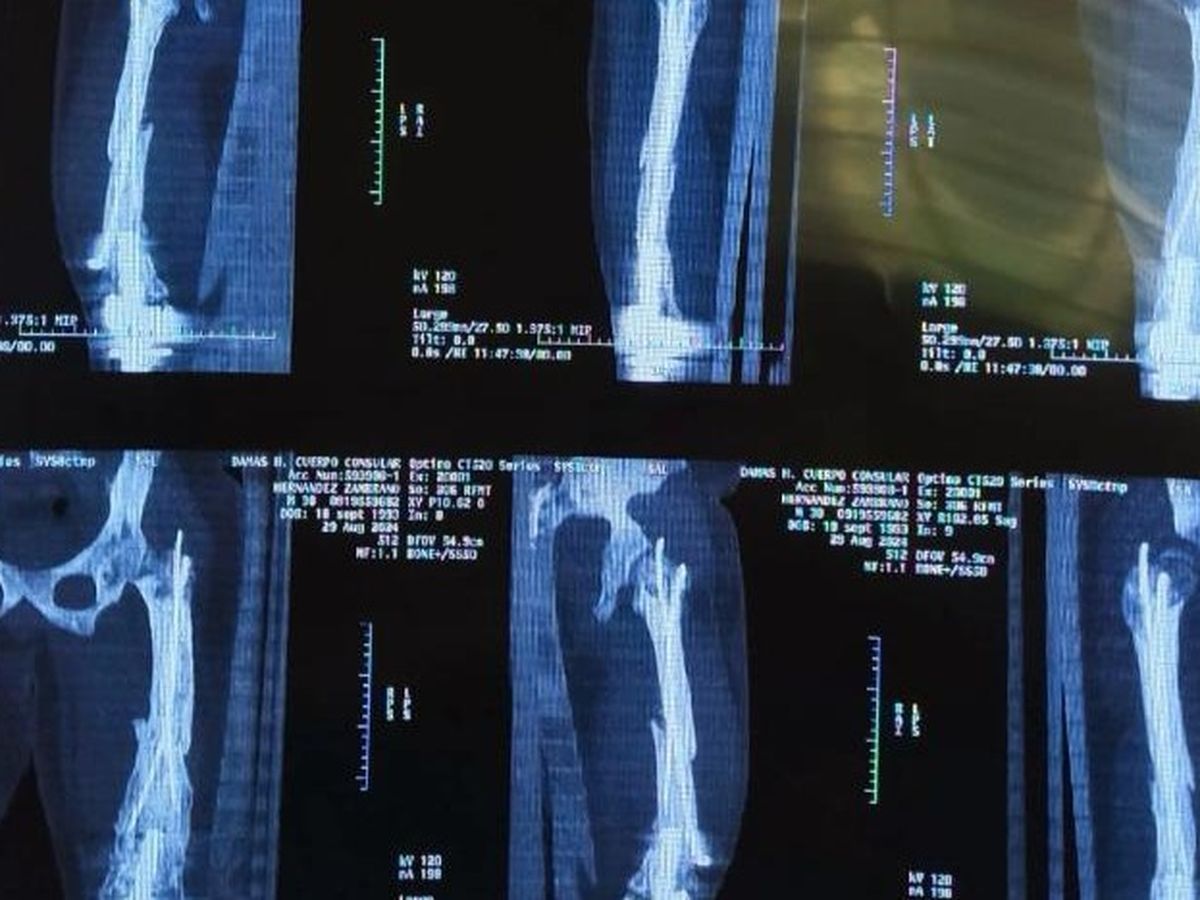

Today we are writing to you with our hearts in our hands to ask for your support in a difficult time for our family. Our son Tito was born with a medical condition known as hypoplasia of the right femur, for which he has required multiple surgeries since he was a baby, until now. Two years ago, he received a knee prosthesis that allowed him to significantly improve, reducing his shortening to just 1 cm.

However, in December 2023, Tito suffered a fracture in his femur, and intramedullary nails were placed to try to stabilize the bone. Unfortunately, the bone is not consolidating and he needs urgent further surgery to correct this complication and allow him to lead a normal, pain-free life.